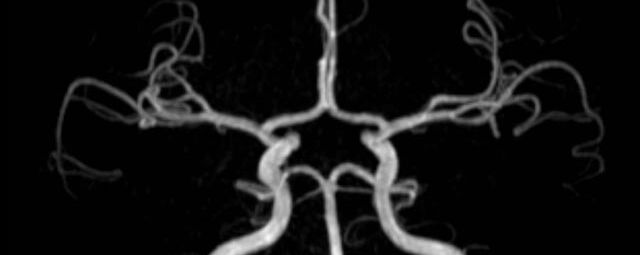

MR-Angiografie (MRA)

• MR-Angiografie ohne Kontrastmittel

• Time of Flight (TOF)-Angiographie

Je nach Fragestellung und Körperregion Gefäßdarstellung ohne Kontrastmittel bei Kontrastmittelunverträglichkeit oder terminaler Niereninsuffizienz möglich.

• MR-Angiographie mit Kontrastmittel

• Erfassung arterieller und venöser Gefäße/Bypässe aller Körperregionen mit 3D-Rekonstruktion